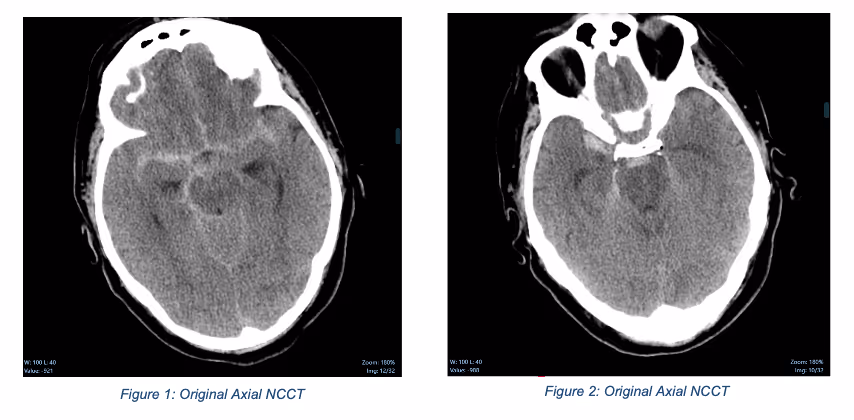

Ferrum Health partners with best-in-class AI providers offering solutions designed to reduce radiology workload and improve patient care.Avicenna Case Study: Acute Subarachnoid HemorrhageHow real-time notification can improve care and efficiency?IntroductionNotification for neuro-critical findings from non-contrast computed tomography (NCCT) imaging of the head can range upwards of 4 hours even in emergency room and critical care settings, which can delay and degrade patient management.Clinical CaseA 61-year-old man presented with altered mental status after being found face down following a fall. Upon presentation, he was alert but remained confused. An NCCT of the head was ordered.

Following imaging acquisition, the case was not reviewed until two hours later, which revealed an acute subarachnoid hemorrhage, predominantly involving the suprasellar cisterns. A follow-up CT angiography was recommended to exclude aneurysmal rupture.

ConclusionThe mean time-to-notification of CINA-ICH is 22s. Had this tool been deployed, the radiologist would have been alerted at the time of imaging. Moreover, he could have immediately reviewed the case and ordered a CTA while the patient still was in the CT scanner while also alerting neuro-critical care teams. Not only could this have improved patient care, but this would have also saved resources.Note: Segmentation is not currently available for clinical use in the United States. Please see Avicenna outputs documents for more information.Intracranial hemorrhages (ICH) affect over two million people worldwidewith a 40-50% patient mortality rate within one month, and 80% disability despite aggressive care.Quick and accurate early diagnosisof ICH mayfacilitate a prompt therapeutic response, allow fast decision-making, and ultimately improve outcomes.CINA-ICH uses deep learning to identify suspected intracranial hemorrhageand prioritizes those cases in the worklist, dramaticallyreducing turnaround time for head traumaand stroke patients.Interested in deploying CINA-ICH at your health facility? Contact the Ferrum Health team to learn more.